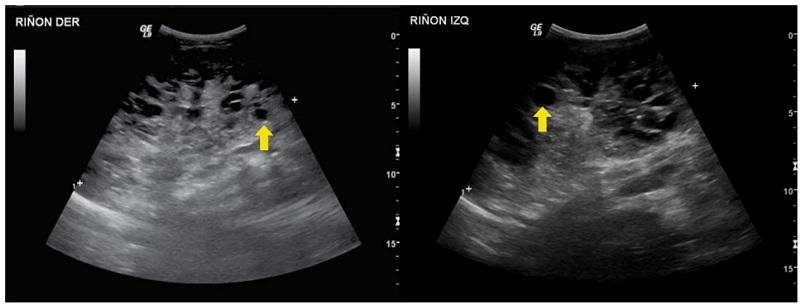

Se trata de una paciente de sexo femenino, producto de una unión no consanguínea, sin antecedentes familiares de relevancia. En una ecografía prenatal en la semana 23 de gestación, se observó el riñón izquierdo con múltiples quistes. Al nacimiento, una ecografía renal y de vías urinarias mostró más de 10 quistes parenquimatosos, bilaterales, distribuidos aleatoriamente, y aumento de la ecogenicidad parenquimatosa, pérdida de la diferenciación corticomedular y disminución en el tamaño del riñón izquierdo (figura 5). La ecografía abdominal total no demostró quistes hepáticos. En el estudio de orina se encontró proteinuria leve.

Por las características clínicas, se sospechó una enfermedad poliquística renal autosómica dominante de presentación neonatal. Se realizó secuenciación de exoma dirigida a genes relacionados con poliquistosis renal, pero no se reportaron variantes patogénicas, por lo que se indicó secuenciación de exoma clínico dado el compromiso renal asociado con manifestaciones extrarrenales, como su fenotipo facial y convulsiones.

Análisis. La enfermedad poliquística renal autosómica dominante es la enfermedad quística renal hereditaria más común, con una incidencia aproximada de dos casos por 1.000 recién nacidos vivos y es una de las principales causas de enfermedad renal terminal 2. Se caracteriza por el desarrollo y expansión progresiva de múltiples quistes a lo largo del parénquima renal, con deterioro paulatino de la función renal que conlleva enfermedad renal terminal cerca de la sexta década de la vida. Usualmente, se diagnostica hacia la segunda o tercera décadas de la vida. Sin embargo, existen presentaciones más tempranas, como la enfermedad poliquística renal autosómica dominante de inicio temprano, que se observa entre los 18 meses y los 15 años; y la enfermedad poliquística renal autosómica dominante de inicio muy temprano, con hallazgo de quistes antes de los 18 meses de vida. Este último grupo corresponde a menos del 1 % de los casos de este tipo de enfermedad poliquística 22.